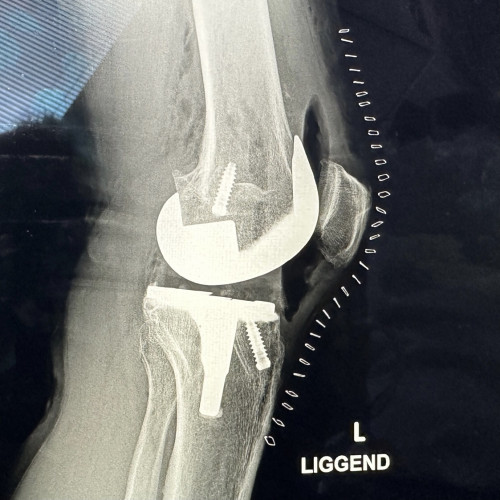

Ben je inmiddels geopereerd? Ik heb een beetje dezelfde uitdaging als jij; fiets ook best veel en heb vorige week een halve knieprotese geplaatst gekregen.

Edit 18:45u, operatie geslaagd. Alles goed gegaan volgens chirurg.

Je hebt fotogenieke knieën